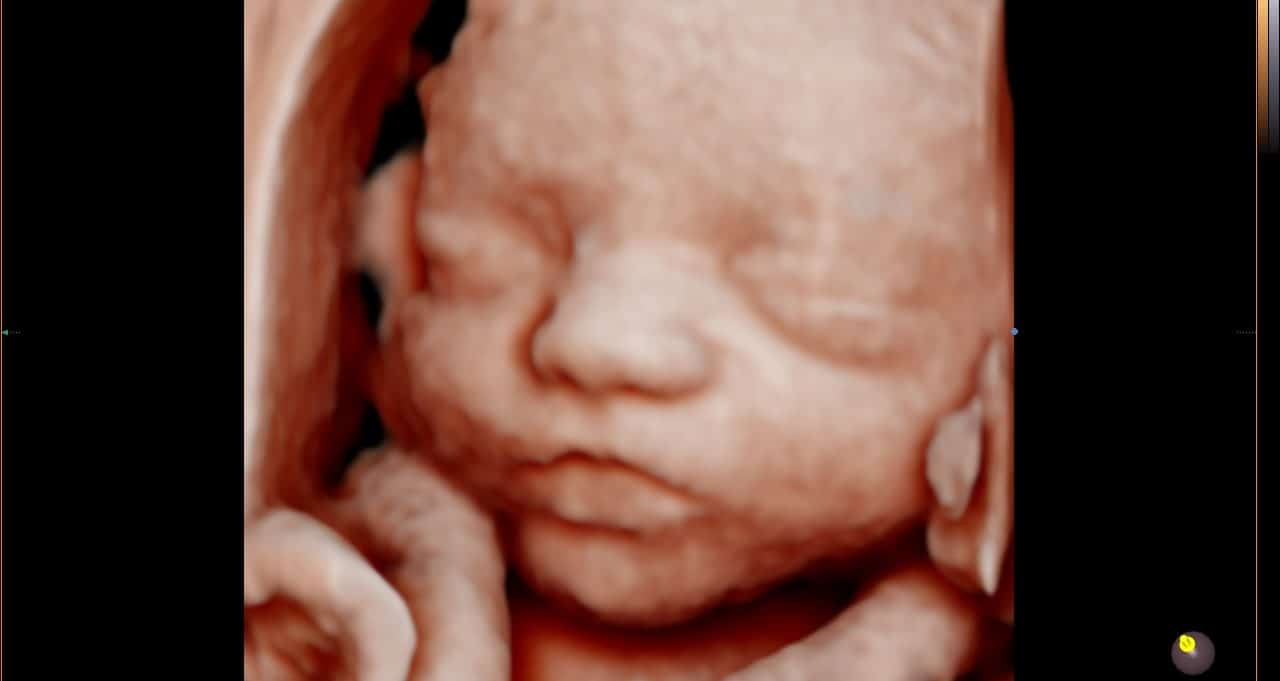

Nesta semana, seu bebê está ganhando peso de forma impressionante, acumulando aproximadamente 225 gramas semanalmente. Ele já pesa entre 1,9 e 2,1 quilos e mede cerca de 43 a 44 centímetros da cabeça aos pés. Este crescimento acelerado é fundamental para o desenvolvimento dos órgãos e sistemas que ainda precisam amadurecer antes do nascimento.

Os movimentos fetais atingem seu pico de intensidade nesta fase da gravidez. Com o espaço cada vez mais restrito no útero, seus chutes e socos podem ser bastante desconfortáveis para você. O líquido amniótico atingiu seu volume máximo, o que significa que há menos “almofada” para amortecer os movimentos do bebê. É normal que você sinta claramente quando ele muda de posição ou se alonga.